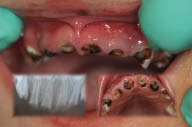

Figure 4-A very severe case of early childhood caries in a young child. Note the paruli present on the buccal gingiva of teeth 52 and 63. All maxillary anterior teeth are unrestorable and require extraction.